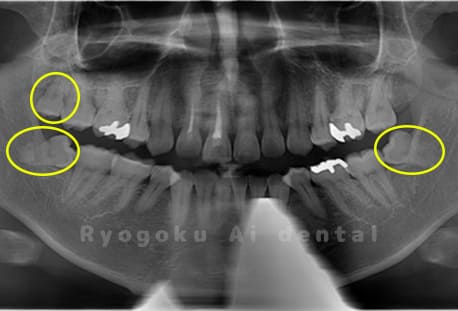

Case04

- 原因

- 上顎の親知らず、下顎の水平埋伏の親知らず

- 治療内容

- 上顎の親知らず、下顎の水平埋伏の親知らずを抜歯したケースです。

<リスク・副作用>

手術後は痛み、腫れ、痺れなどの副作用が生じる場合があります。